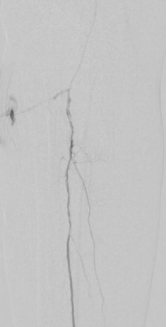

6. 股浅动脉下段置入6-150mm载药支架,于股浅动脉中上段置入6-220、 6-150mm载药球囊扩张

7. 术后造影血流恢复